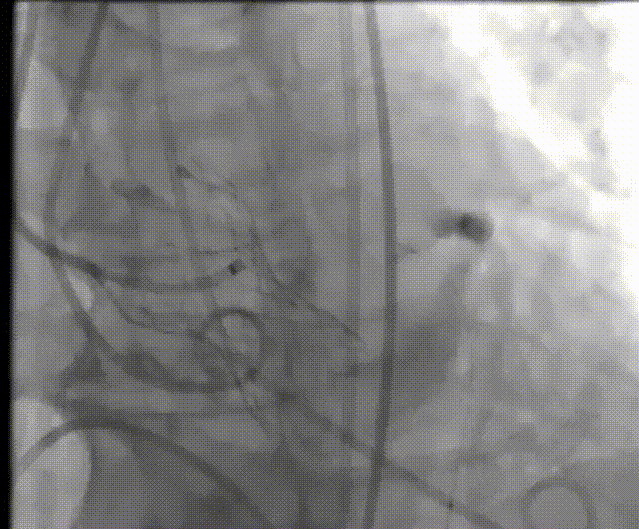

袁义强教授 河南省胸科医院(点击查看专家详细简历) 拥抱创新技术,推动心血管诊疗革新:作为医院管理者,我们团队始终把患者需求放在首位。干瓣作为TAVR的全新一代产品,其抗钙化性能预期为临床带来更卓越的耐久性,进一步延缓及降低二次手术的发生,每一个殷切期待眼神的患者身上,我们始终警醒,尽全力减少患者反复就医的痛苦,更从长远大幅节约医疗开支,让普通家庭看得起病、看好病。这不仅提升了诊疗效果,更践行了医疗惠民的初心,也多层面地减少医疗资源重复投入,为构建更经济高效的医疗体系注入动力,切实守护群众健康福祉。 孙玉梅教授 河南省胸科医院(点击查看专家详细简历) 念兹在兹,护佑患者每一刻:从医多年,我始终记得患者躺在病床上眼里饱含对健康渴求的殷切眼神,这是对医者的全心信赖——是把生命全然托付的信任,这份沉甸甸的情意,怎能辜负?选择什么手术策略,选择什么产品,医者需要给到专业意见的同时也需要听取患者的内心需求,既要保证当下手术的顺利成功,术后的快速恢复,更要为患者的长远生活兜底。Prostyle A 在这例重度钙化患者身上,既实现了术中安全植入、术后即刻改善,长久的抗钙化性能预期可以护航患者长期的生活。这份 “即刻与长久” 的平衡,正是我们一切从患者出发的初心写照,唯愿每一个细节里,都藏着让患者踏实的温度。 患者病史 主诉:间断胸闷、气促3年,加重两天。 既往史:平素健康状况良好。16 年前出现言语不清,就诊于当地医院,诊断为“脑梗死”给予药物治疗后症状好转。 术前 CT:Type1型(R-N)二叶瓣,右无交界存在钙化脊、粘连融合,极重度钙化,钙化集中在右无交界及三窦瓣叶边缘。 瓣环径27.1mm,LVOT28.9mm,瓣上3mm、6mm、9mm、12mm限制逐渐加重,从27mm逐渐缩窄至21mm。VTC空间较小,有一定冠脉风险。外周入路散在钙化、集中在双侧髂动脉与右股穿刺点后壁、双侧入路无明显迂曲,右股动脉内径可、低分叉。 手术策略 推荐右侧股动脉为主入路,瓣环27.1mm,Type1型(R-N)二叶瓣,右无交界存在钙化脊、粘连融合,极重度钙化,建议使用20mm球囊预扩,预装可回收AV23主动脉瓣膜,初始定位推荐真实瓣环上5mm超高位释放,释放时卸张力使瓣膜自然下滑至约瓣上1mm,利用瓣上限制固定瓣膜,提高封堵区封堵瓣上交界处,释放至工作位观察瓣膜情况决定是否回收。 手术过程 左右冠置入导丝进行冠脉保护 20号球囊预扩无明显腰征微量返流 初始定位 80%工作位观察 20号球囊后扩无明显腰征微量返流 术后造影:瓣膜形态好,有少量瓣周漏,冠脉造影无堵塞 术后超声:瓣膜形态好,有少量瓣周漏,平均跨瓣压差5mmHg Prostyle A®预装干瓣——“稳定支撑”助力临床最优化解决方案: 1. 平衡的径向支撑力:Prostyle A®综合设计带来平衡的径向支撑力,释放张力小,稳定贴靠,轻松应对高钙化病变; 2. Micro-EX™专利抗钙化技术:金仕生物专利抗钙化技术运用纳米技术去除组织内的细胞碎片和磷脂,封闭游离醛基,从根本上阻断了瓣膜钙化的多项因素,显著提升了瓣膜的耐久性;同时,相比较传统戊二醛保存方式,干式存储最大限度的保留心包的亲水亲油平衡,还原组织天然曲柔性,进一步保障了瓣叶开合,保证长期耐久性; 3. Prostyle A®平衡收腰设计:该例患者存在冠脉风险,Prostyle A®环上瓣及平衡的收腰设计,术后冠脉造影无堵塞,保证了有效瓣口面积的同时,带来更优异的血流动力学。